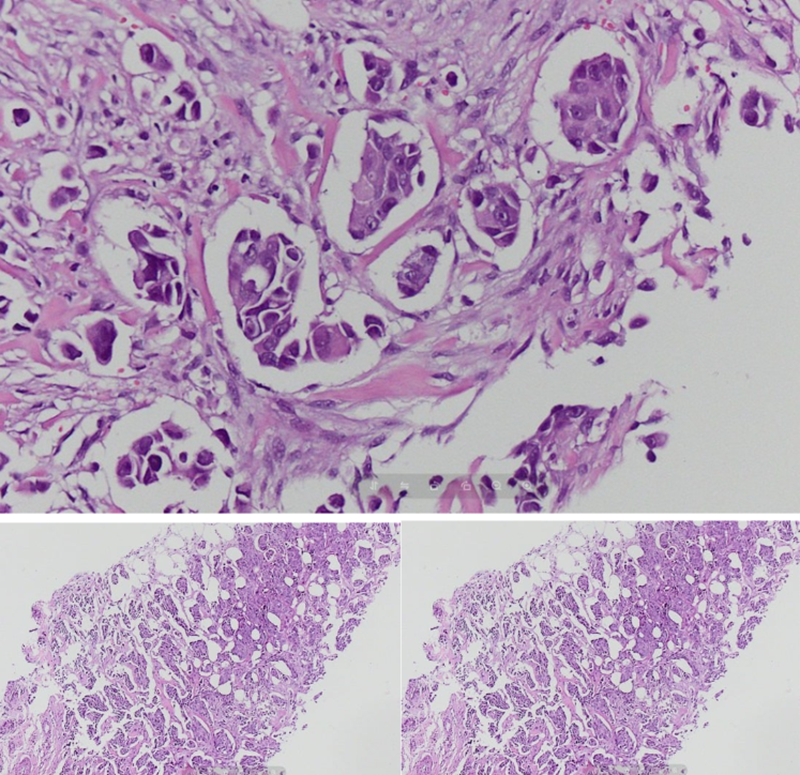

Để xác định chính xác bản chất tổn thương, PGS. Nghị đã chỉ định thực hiện sinh thiết dưới hướng dẫn của siêu âm. Mẫu bệnh phẩm nhanh chóng được chuyển tới Trung tâm Giải phẫu bệnh MEDLATEC để phân tích chuyên sâu.

Kết quả xét nghiệm mô bệnh học thường quy (nhuộm Hematoxylin - Eosin) xác định bệnh nhân mắc Carcinoma tuyến vú thể ống xâm nhập (NST), độ mô học II.

Xét nghiệm mô bệnh học xác định bệnh nhân mắc Carcinoma tuyến vú thể ống xâm nhập

Tuy nhiên, để đánh giá chính xác tiên lượng và xây dựng phác đồ điều trị tối ưu, cần thực hiện thêm xét nghiệm hóa mô miễn dịch (HMMD) với bộ 4 dấu ấn đặc hiệu (ER, PR, HER-2, Ki-67). Kết quả đây là Carcinoma tuyến vú xâm nhập, phân típ phân tử lòng ống B (Luminal B), HER-2 dương tính 3+.

Căn cứ vào kết quả trên, bác sĩ chẩn đoán bà T. mắc ung thư tuyến vú biểu mô thể ống xâm nhập, độ mô học II.